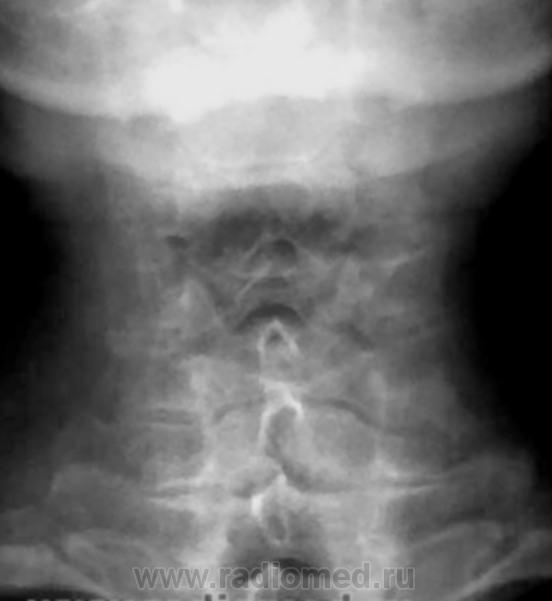

Остеохондроз, спондиллоартроз, протрузия МПД С5-С6 кзади. Что Вас смущает на этих снимках? Игра теней на уровне С6(прямой снимок)?

В теле С5 поперечное посветление в боковой, видимо и в прямой проекции.

Неоартроз+склероз обусловили линейные тени в проекции тела С5.

Переспав с мыслью родилась идея. Ведь пергрузочная болезнь может возникать и в телах позвонков. В теле С5 в данном случае зона просветления, которая не персекает полностью тело позвонка, а опоясывает, развиваясь под надкостницей. Края ее ровные, как бы поясок вокруг тела.Плотность тела позвонка увеличена, вероятно за счет компенсаторного капиллярного кровотока вокруг зоны перестройки. В данном случае, перегрузочная болезнь, вероятно, возникла как компенсаторный процесс в ответ на изменение оси нагрузки, либо, еще в молодом возрасте.как Признаю, игра теней и артроз не в тему.

На теле С5 вероятно изображение унко-вертебрального артроза. Это его законное место. В прямой проекции вообще толком ничего не видно. Снимки очень неважные. Почему ваши лаборанты так широко раскрыли диафрагму? Качество очень страдает. Если есть сомнения в бабочковидном позвонке, можно сделать прямую томограмму.

Валентин Львович, то, что Вы пометили желтыми стрелками, изображения оснований поперечных отростков, они есть и в других позвонка. Снизу идут ножки дуг, которые накладываются на задние отделы тел и их плотные контуры делают визуально верхний угол тела более прозрачным. Это игра теней.

Для Goncharovakuraeva : я изменения описал как дистрофические, а посветление в теле С5, предположительно расценил как дисластические (типа фиброзной прослойки в теле позвонка).

Для Nela: я то же рассмтривал версию, что просветление в теле С5, за счёт унковертебрального артроза, но мне представляеться, что в последенем случае картина, несколько иная.

Линейное просветление горизонтального характера есть аномалия развития...просто в шейном отделе сие встречается крайне редко, чаще в груднои или плясничном, а фактически - канал артерии...

Щель то щелью, но она должна располагаться посредине тела, а здесь несколько смещена каудально. Кроме того, если в грудном и поясничном отделах сосудистая щель или канал встречаются очень часто, то в шейных позвонках не разу не видела.

У меня, то же была мысль, что посетление в теле позвонка. возможно за счёт канала питающего сосуда. но там (книга И.П.Королюка) картинка не совсем такая, так как в последнем случае, борозда начинаеться с заденго края тела позвонка, данном случае мы этого не видим ( жаль пока не могу вставлять картинки в посты).

Щелевидный дефект (или линейное горизонтальное просветление) ничем больше не обьяснить, как наличием сосуда...что касаемо корифеев, так на то оно и корифеи, чтобы строить дом, а мы - практики - чтобы в нем щели латать...оставшиеся после строителей...при всем к НИМ уважении...снимем шляпы, но оставим головы...

По всей видимости, о "питающем" сосуде или о его канале говорить нереально, так как для этого необходимо высокоструктурное изображение.

По данным снимкам сие недоказуемо. Надо делать лин. томографию.